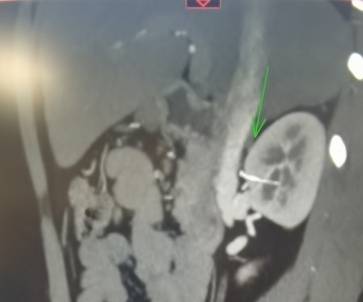

影像检查结果发现患儿右肾前上极内见一金属物,从肾前插入肾实质内,深度约23毫米,肾外段2毫米,位于肾门与下腔静脉之间,右肾静脉与动脉上方约8毫米。接诊医师陈征副教授结合影像检查结果详细追问病史。

泌尿外科团队经过细致讨论和周密计划后,采用腹腔镜技术,术中通过精细解剖,突破重重难关,历经一个半小时,完整取出患儿右肾金属物,金属物为一根针,长约26毫米,手术全程无出血。术后泌尿外科医护团队鼓励患儿早期进食、早期下床活动。经过医护人员精心护理及患儿家属的积极配合,患儿术后第3天顺利康复出院。